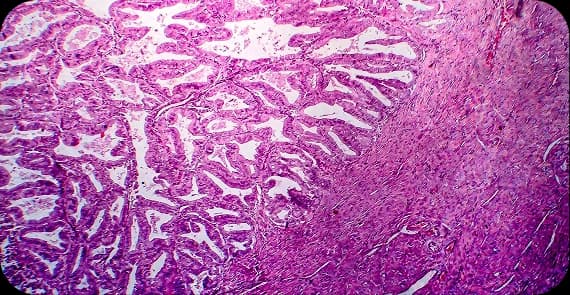

When patients seek to understand early-stage uterus cancer, the explanation begins at the cellular level. Uterine cancer most commonly starts in the inner lining of the uterus, known as the endometrium. This is often referred to as endometrial cancer.

There are different types of uterus cancer depending on the tissue involved.

The most common type, arising from the lining of the uterus.

A rare type that develops in the muscle or supporting tissues of the uterus.

This category includes mixed histology tumours, which exhibit more aggressive behaviour.